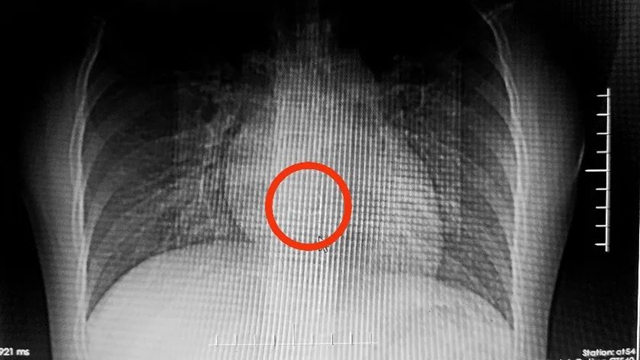

急诊科何文扬医生立即联系了正在上门诊的消化内科副主任(主持工作)钟晓琳教授。为了明确异物的情况,影像科立即为女孩拍了CT片,发现这颗牙套长约3厘米,带有弯曲的钢丝,卡在了食管中段狭窄处(心脏水平)。

更可怕的是,从影像片子上看,牙套上的钢丝可能已经刺破食道,紧邻主动脉,又由于金属在摄片时会产生伪影,很难判断钢丝尖端和主动脉的关系,不除外已经穿入主动脉的可能。